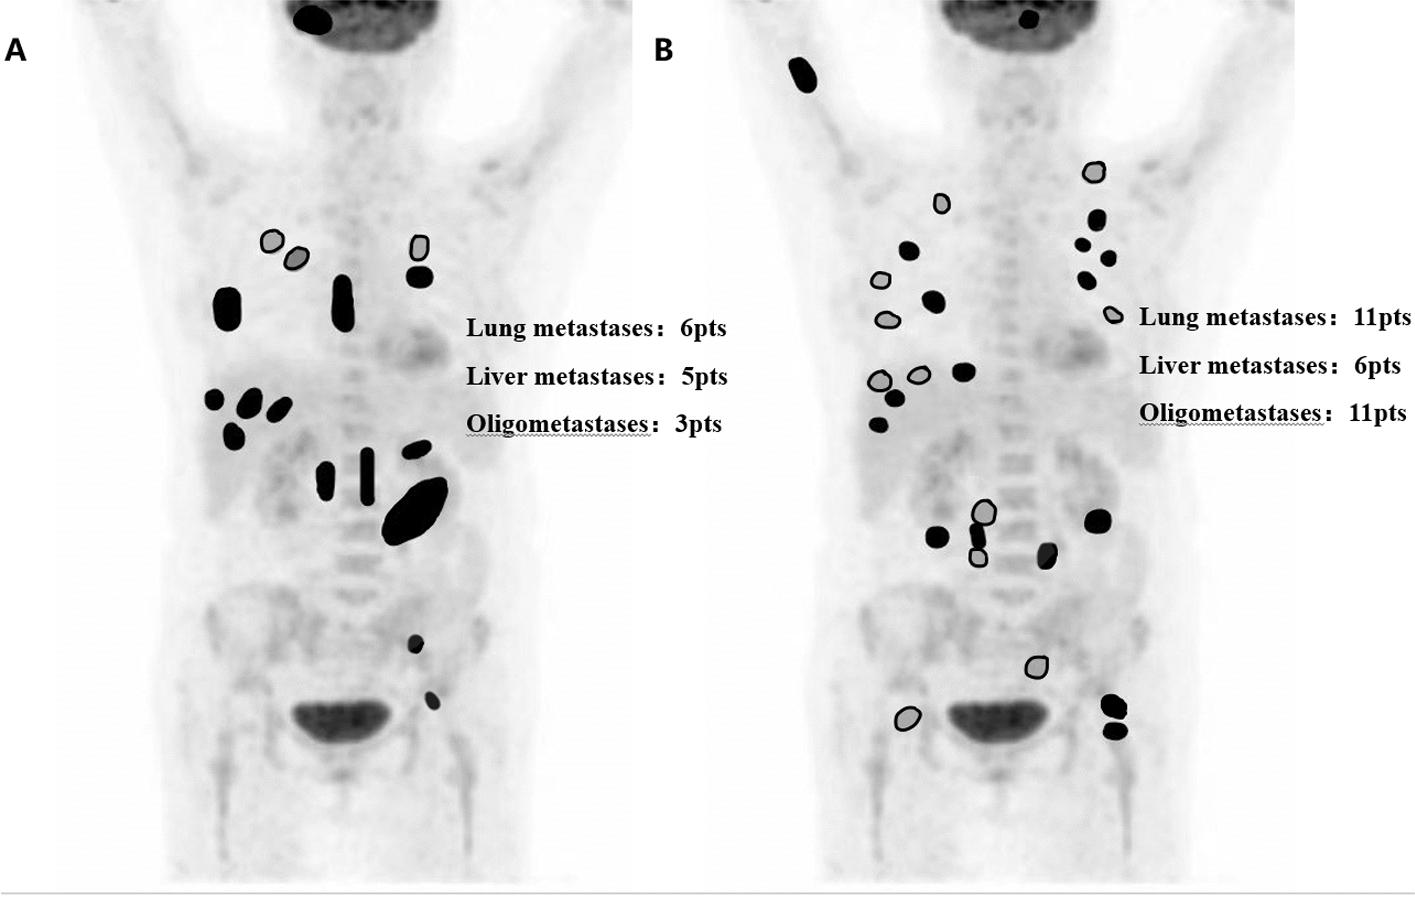

A total of 651 LARC patients were included, 160 (24.6%) of whom had positive LPLN and 491 (75.4%) had negative LPLN. Before PSM, the LPLN-positive group had higher rates of lower location (53.1% vs. 43.0%, P = 0.025), T4 stage (37.5% vs. 23.2%, P = 0.002), mesorectal fascia (MRF)-positive (53.9% vs. 35.4%, P < 0.001) and extramural venous invasion (EMVI)-positive (51.2% vs. 27.2%, P < 0.001) disease than the LPLN-negative group. After PSM, there were 114 patients for each group along with the balanced clinical factors, and both groups had comparable surgery, pathologic complete response (pCR), and ypN stage rates. The median follow-up was 45.9 months, 3-year OS (88.3% vs. 92.1%, P = 0.276) and LRR (5.7% vs. 2.8%, P = 0.172) rates were comparable between LPLN-positive and LPLN-negative groups. Meanwhile, despite no statistical difference, 3-year PFS (78.8% vs. 85.9%, P = 0.065) and DM (20.4% vs. 13.3%, P = 0.061) rates slightly differed between the groups. 45 patients were diagnosed with DM, 11 (39.3%) LPLN-positive and 3 (17.6%) LPLN-negative patients were diagnosed with oligometastases (P = 0.109).

共纳入651例LARC患者,其中160例(24.6%)LPLN阳性,491例(75.4%)LPLN阴性。PSM前,LPLN阳性组低位病变(53.1%对43.0%,P = 0.025)、T4期(37.5%对23.2%,P = 0.002)、直肠系膜筋膜(MRF)阳性(53.9%对35.4%,P < 0.001)及壁外静脉侵犯(EMVI)阳性(51.2%对27.2%,P < 0.001)疾病的发生率高于LPLN阴性组。PSM后,每组各有114例患者且临床因素得到平衡,两组在手术、病理完全缓解(pCR)及ypN分期率方面具有可比性。中位随访时间为45.9个月,LPLN阳性组与LPLN阴性组的3年总生存率(88.3%对92.1%,P = 0.276)和局部区域复发率(5.7%对2.8%,P = 0.172)具有可比性。同时,尽管无统计学差异,但两组的3年无进展生存率(78.8%对85.9%,P = 0.065)和远处转移率(20.4%对13.3%,P = 0.061)略有不同。45例患者被诊断为远处转移,11例(39.3%)LPLN阳性患者和3例(17.6%)LPLN阴性患者被诊断为寡转移(P = 0.109)。